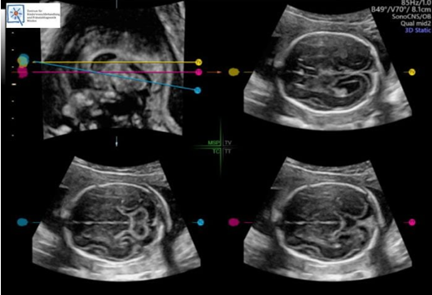

Dr. Ralf Menkhaus ve çalışma arkadaşları, bir süredir GE Sağlık’ın fetüs beyin değerlendirmesini ve ölçümlerini otomatikleştiren yapay zekâ aracı SonoCNS’yi kullanıyor.

Fetüs Tıbbı Uzmanı Dr. Ralf Menkhaus ana rahmindeki bebekler için sorun belirtisi olup olmadığını saptamak üzere ultrason görüntülerini inceliyor. Örneğin, omuriliği etkileyen bir nöral tüp defekti olan ve doktorların fetal beyindeki değişiklikler gibi ipuçlarına dayanarak hamileliğin yaklaşık 20. haftasında teşhis edilebilen spina bifida gibi. Ancak fetal beyin ölçümleri, tecrübeli doktorların birden çok metriği dikkate almak zorunda olduğu ve kesinliği düşük sayılabilecek bir bilim. Bir sonografi uzmanının değerlendirmesi diğerinden farklı olabildiğinden, hatalı veya gecikmiş tanılara yol açabiliyor. Menkhaus, GE Sağlık‘ın fetal beyin değerlendirmesini ve ölçümlerini otomatikleştiren yapay zekâ aracı SonoCNS teknolojisi ile süreci basitleştirebileceğini duyduğunda oldukça rahatladığını belirtiyor. SonoCNS, GE Sağlık‘ın bulut tabanlı uygulama geliştirme, veri depolama ve analiz platformu Edison aracılığıyla eğitildi. Menkhaus, bu teknolojinin daha az tecrübeli jinekologlar için özellikle faydalı olduğunu belirtiyor: “Artık, tek bir düğmeye basarak doğru ve güvenilir ölçümlere erişebilecekler.”